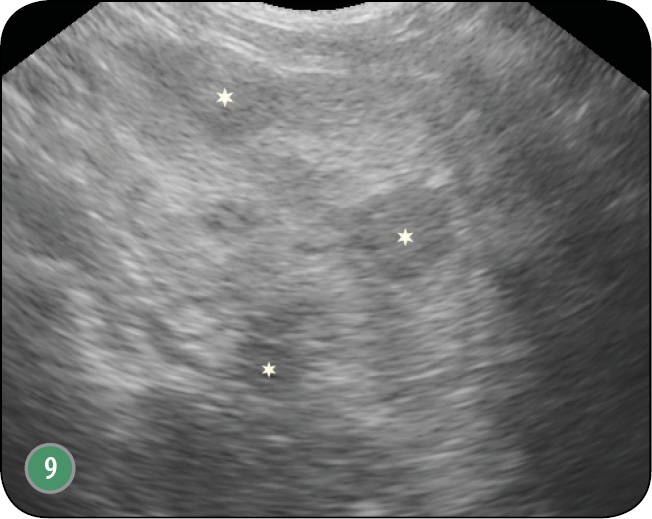

W obrazie ultrasonograficznym zmienionego nowotworowo gruczołu krokowego może wystąpić wiele zmian. Gruczoł zwykle ulega znacznemu powiększeniu, utkanie miąższu bywa często niejednorodne (ryc. 8), występują hiper- i hipoechogeniczne obszary (ryc. 9) (1, 4, 7, 12, 16, 21, 26, 30). Obserwuje się również zmiany jamiste o szorstkich krawędziach, zmiany lite o utkaniu tkankowym, jedno- lub wieloogniskowe (ryc. 4b). Nierzadko widoczne są hiperechogenne echa z cieniem akustycznym, które świadczą o obecności zwapnień (ryc. 10).